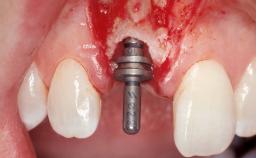

Late Flapless Placement of an Implant in a Maxillary Left Central Incisor Site

A 39-year-old male patient presented with a chief complaint of discomfort and gingival discoloration around his maxillary left central incisor. He was in good general health and was a non-smoker. His past dental history was significant because of the traumatic fracture of tooth 21 in a sporting accident at age 13. Initial dental treatment included endodontic therapy and a full-coverage restoration. The patient became symptomatic 5 years later, when structural failure of the tooth resulted in the dislodgment of the crown. Endodontic retreatment, apical surgery, and post-and-core restoration were performed.

Type of Implants One-Piece

Attachment One-Piece

Abutment Type Standard

Placement Protocol Early or late implant placement